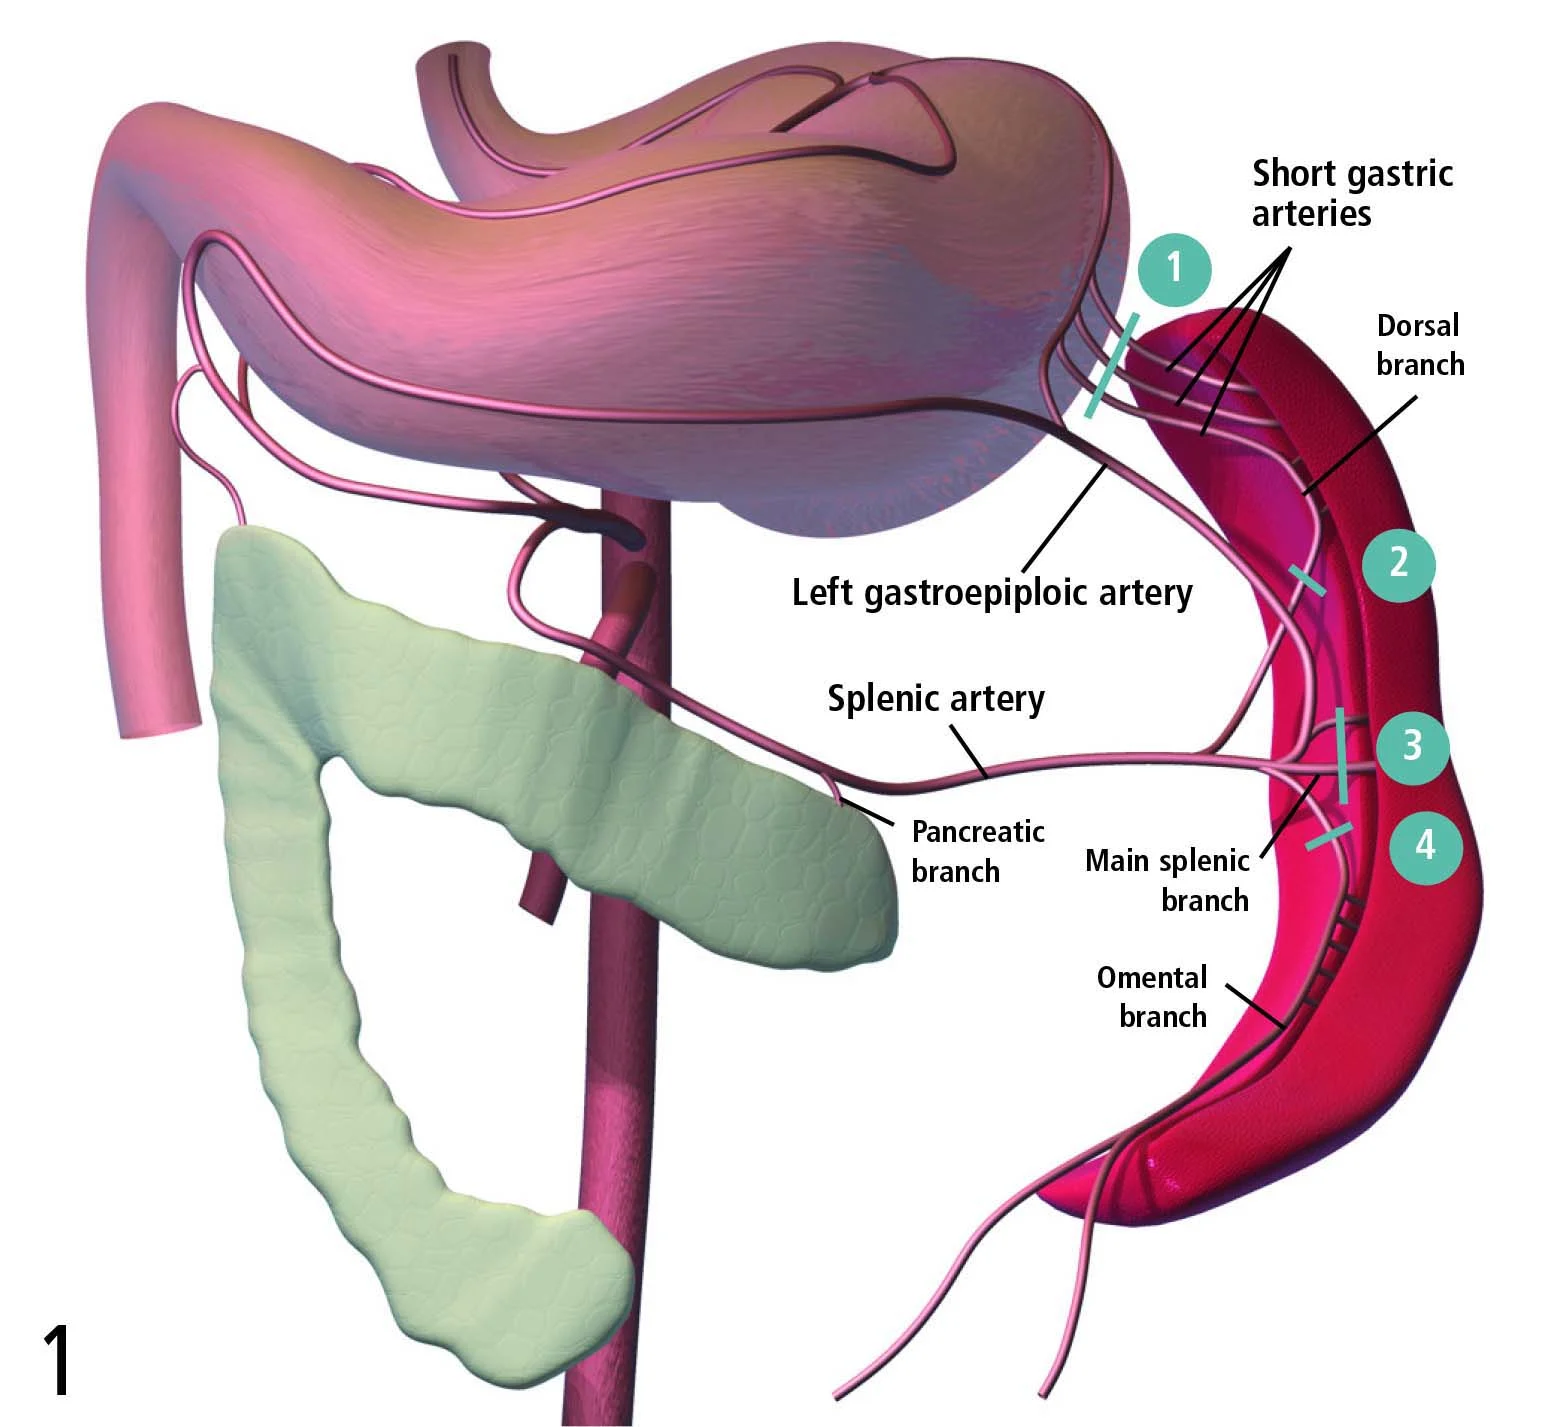

Anatomy & Ligation

Three to 5 long, rather consistent primary blood vessel divisions of the splenic artery are the most important vascular structures to know before considering splenectomy (Figure 1). The most common textbook description for splenectomy includes individual ligation of short branches of the splenic artery and vein, preserving the left gastroepiploic artery and short gastric arteries, to maintain adequate gastric perfusion. In an experiment by Hosgood using healthy mixed-breed dogs, splenic and short gastric artery ligation during splenectomy did not compromise blood flow or the integrity of the stomach wall. Therefore, most surgeons are not concerned about ligation of these vessels, provided the stomach wall is not compromised. In conditions known to adversely affect gastric blood supply, such as acute gastric dilatation-volvulus, preservation of existing gastric perfusion during splenectomy is an important goal.

Diagram showing splenic arterial supply and 4 proposed ligation areas (blue lines).

The final 3 pedicles are isolated with the index finger, cross-clamped, and incised in the following order (refer to Figure 1): · Dorsal artery branch (Sometimes there are 2; be careful to preserve the left gastric epiploic artery located close to this branch.) · Main splenic artery terminating in the mid portion of the spleen · Caudal (omental) branch coursing along the tail of the spleen to the greater omentum.